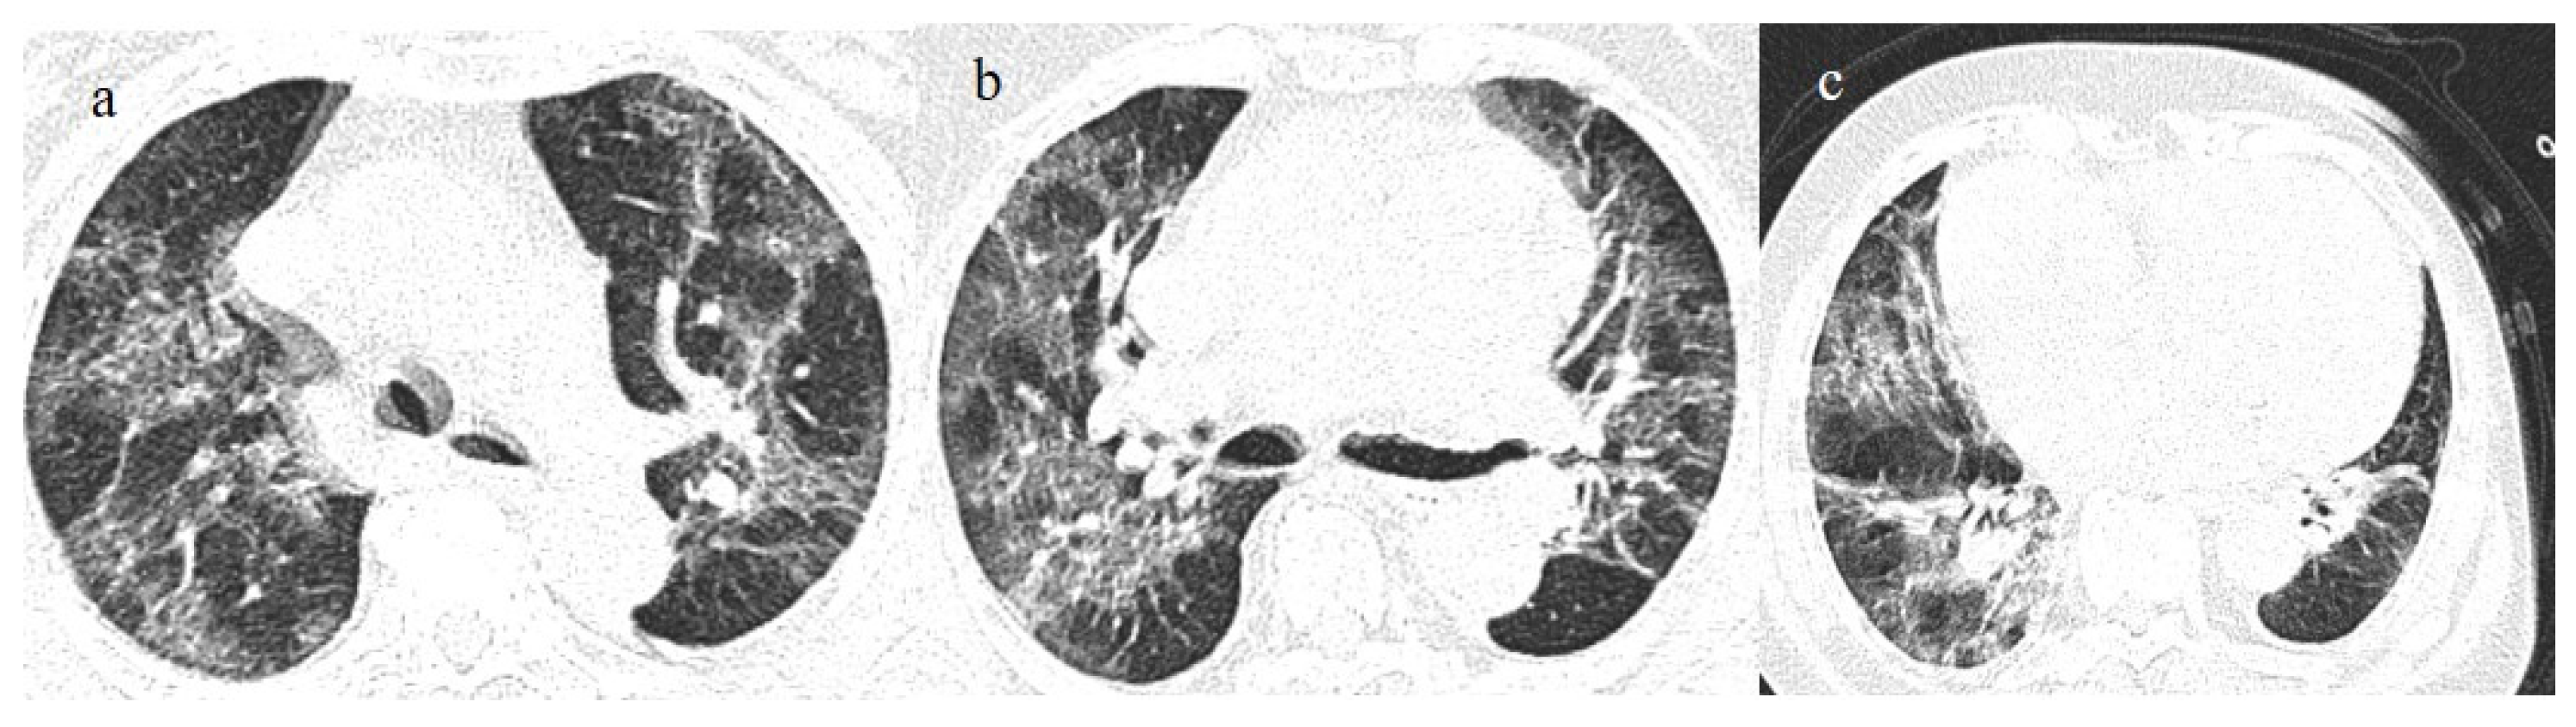

- Melhorn, J.; Achaiah, A.; Conway, F.M.; Thompson, E.M.; Skyllberg, E.W.; Durrant, J.; Hasan, N.A.; Madani, Y.; Naran, P.; Vijayakumar, B.; et al. Pneumomediastinum in COVID-19: A phenotype of severe COVID-19 pneumonitis? The results of the United Kingdom (POETIC) survey. Eur. Respir. J. 2022, 60, 2102522. [Google Scholar] [CrossRef]

- Khaire, N.; Deshmukh, S.; Agarwal, E.; Mahale, N.; Khaladkar, S.; Desai, S.; Kulkarni, A. “Pneumomediastinum: A marker of severity in COVID-19 disease”. Heliyon 2023, 9, e12981. [Google Scholar] [CrossRef] [PubMed]

- Tetaj, N.; Garotto, G.; Albarello, F.; Mastrobattista, A.; Maritti, M.; Stazi, G.V.; Marini, M.C.; Caravella, I.; Macchione, M.; De Angelis, G.; et al. Incidence of Pneumothorax and Pneumomediastinum in 497 COVID-19 Patients with Moderate–Severe ARDS over a Year of the Pandemic: An Observational Study in an Italian Third Level COVID-19 Hospital. J. Clin. Med. 2021, 10, 5608. [Google Scholar] [CrossRef] [PubMed]

- Kecskes, G.; Szabo, A.; Sutori, D.; Maroti, P.; Marovics, G.; Molnar, T.F. Pneumothorax/pneumomediastinum and pre-existing lung pathology in ventilated COVID-19 patients: A cohort study. J. Thorac. Dis. 2022, 14, 4733–4740. [Google Scholar] [CrossRef] [PubMed]

- Dubey, R.; Sen, K.K.; Mishra, A. Barotrauma and its complications in COVID-19 patients: A retrospective study at tertiary care hospital of Eastern India. Bull. Natl. Res. Cent. 2022, 46, 1–8. [Google Scholar] [CrossRef] [PubMed]

- Capaccione, K.M.; D’souza, B.; Leb, J.; Luk, L.; Duong, J.; Tsai, W.-Y.; Navot, B.; Dumeer, S.; Mohammed, A.; Salvatore, M.M. Pneumothorax rate in intubated patients with COVID-19. Acute Crit. Care 2021, 36, 81–84. [Google Scholar] [CrossRef]

- McGuinness, G.; Zhan, C.; Rosenberg, N.; Azour, L.; Wickstrom, M.; Mason, D.M.; Thomas, K.M.; Moore, W.H. IncreaIncidence of Barotrauma in Patients with COVID-19 on Invasive Mechanical Ventilation. Radiology 2020, 297, E252–E262. [Google Scholar] [CrossRef]

- Martinelli, A.W.; Ingle, T.; Newman, J.; Nadeem, I.; Jackson, K.; Lane, N.D.; Melhorn, J.; Davies, H.E.; Rostron, A.J.; Adeni, A.; et al. COVID-19 and pneumothorax: A multicentre retrospective case series. Eur. Respir. J. 2020, 56, 2002697. [Google Scholar] [CrossRef]

- Rodriguez-Arciniega, T.G.; Sierra-Diaz, E.; Flores-Martinez, J.A.; Alvizo-Perez, M.E.; Lopez-Leal, I.N.; Corona-Nakamura, A.L.; Castellanos-Garcia, H.E.; Bravo-Cuellar, A. Frequency and Risk Factors for Spontaneous Pneumomediastinum in COVID-19 Patients. Front. Med. 2021, 8, 662358. [Google Scholar] [CrossRef]

- Zantah, M.; Castillo, E.D.; Townsend, R.; Dikengil, F.; Criner, G.J. Pneumothorax in COVID-19 disease- incidence and clinical characteristics. Respir. Res. 2020, 21, 1–9. [Google Scholar] [CrossRef]

- Shahsavarinia, K.; Rahvar, G.; Soleimanpour, H.; Saadati, M.; Vahedi, L.; Mahmoodpoor, A. Spontaneous pneumomediastinum, pneumothorax and subcutaneous emphysema in critically ill COVID-19 patients: A systematic review. Pak. J. Med. Sci. 2022, 38, 730–735. [Google Scholar] [CrossRef]

- Hamouri, S.; AlQudah, M.; Albawaih, O.; Al-Zoubi, N.; Syaj, S. Spontaneous pneumothorax, pneumomediastinum and subcutaneous emphysema in non-ventilated COVID-19 patients. Futur. Sci. OA 2022, 8, FSO771. [Google Scholar] [CrossRef]

- Shaikh, N.; Al Ameri, G.; Shaheen, M.; Abdaljawad, W.I.; Al Wraidat, M.; Al Alawi, A.A.S.; Ali, H.S.; Mohamed, A.S.; Daeri, H.; Khatib, M.Y.; et al. Spontaneous pneumomediastinum and pneumothorax in COVID-19 patients: A tertiary care experience. Health Sci. Rep. 2021, 4, e339. [Google Scholar] [CrossRef]

- Gandolfo, C.; Bonfiglio, M.; Spinetto, G.; Ferraioli, G.; Barlascini, C.; Nicolini, A.; Solidoro, P. Pneumomediastinum associated with severe pneumonia related to COVID-19: Diagnosis and management. Minerva Medica 2022, 112, 779–785. [Google Scholar] [CrossRef]

- Espinosa, C.; Morente, L.M.; Mansour, E.H.; Yousefzadeh, M.L.; Muzaffarr, Z.M.; Salguero, D.; Vianna, S.D.; Quesada, L.D.; Poli, S.; Garcia, H. Predictors of Spontaneous Pneumomediastinum in Patients with COVID-19 and Ards on High-Flow Nasal Cannula. Chest 2022, 162, A1360–A1361. [Google Scholar] [CrossRef]

- Coppola, M.G.; Lugarà, M.; Tamburrini, S.; Madonna, P.; Panico, C.; Noschese, G.; Pone, E. Pneumomediastinum and Pneumothorax as Relevant Complications of Sub-Intensive Care of Patients with COVID-19: Description of a Case Series. Medicina 2021, 57, 919. [Google Scholar] [CrossRef]

- Palumbo, D.; Campochiaro, C.; Belletti, A.; Marinosci, A.; Dagna, L.; Zangrillo, A.; De Cobelli, F. Pneumothorax/pneumomediastinum in non-intubated COVID-19 patients: Differences between first and second Italian pandemic wave. Eur. J. Intern. Med. 2021, 88, 144–146. [Google Scholar] [CrossRef]